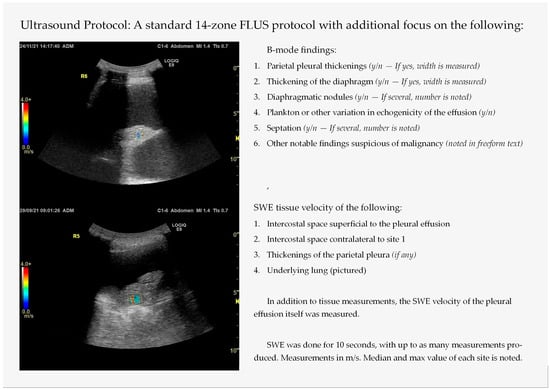

The included patients underwent a thoracic ultrasound examination, based on the 14-zone focused lung ultrasound (FLUS) protocol previously validated for an emergency setting [18,19,20]. However, special emphasis was put on a set of B-mode findings, to assess whether they were associated with malignancy or whether an effusion is of exudative or transudative nature, see Figure 1. Earlier studies suggest a parietal pleural thickening larger than 1 cm and a nodular diaphragm thicker than 7 mm as optimal cutoff points to determine malignancy [12]. Notable findings suggestive of malignancy were regarded as lung tissue with limited/incomplete ‘fish-tail’ atelectasis despite massive effusions or varied echogenicity/heterogenicity of lung tissue not similar to typical pneumonia (hepatization of lung tissue with or without air bronchograms) [21,22,23,24]. After the B-mode scan, the patients underwent SWE, and the tissue shear wave velocity was recorded by regions of interest (ROIs) superimposed on areas specified in Figure 1.

Figure 1. The ultrasound protocol used in this study, modified from the focused lung ultrasound (FLUS) protocol. SWE = shear wave elastography. Both sonographs pictured are of SWE of a lung atelectasis.